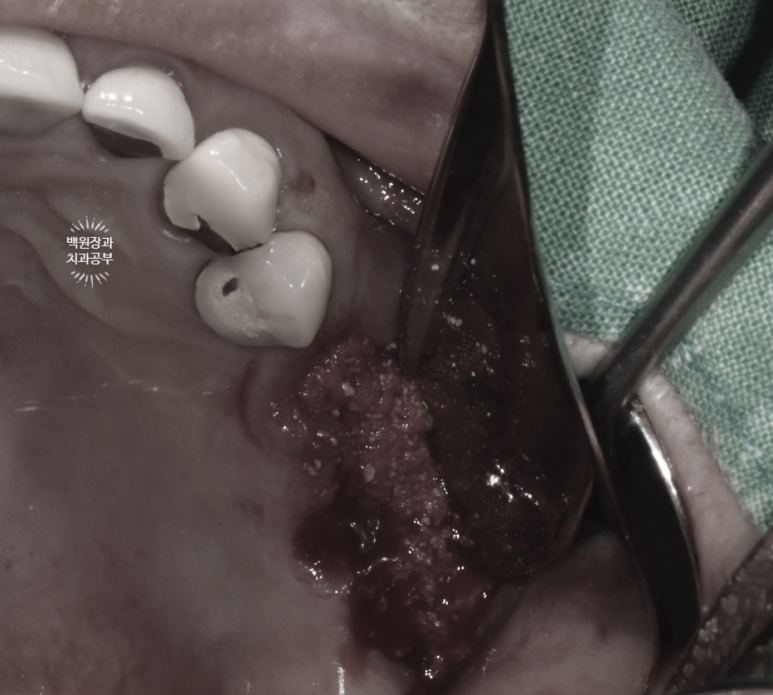

임플란트를 제거할 당시의 사진입니다.

회색으로 보이는 나사선이 임플란트 고정체 (fixture)의 본체이며, '당연히' 뼈 속에 묻혀 있어 보이지 않아야 하는 부분입니다.

수 년간 만성임플란트주위염의 결과로써 치주농양이 형성되었고, 치조골은 사라지고 노출된 임플란트만 남았네요.....

일반적으로, 임플란트 픽스쳐 (fixture)의 50프로 이상 수직골소실이 생기면

제거하고 다시 수술 받으시길 권해드립니다.

임플란트 주위염에 시달리고 있는 임플란트를 너~무 늦게 제거하게 되면,

사정없이 주변 잇몸뼈가 사라지게 되고.... 그러면 다시 임플란트를 하기에도 난감한 수준으로 뼈가 사라져 버려요.

보면 제거된 임플란트 주변에 뼈는 없고, 염증조직만 가득한 것을 볼 수 있네요...